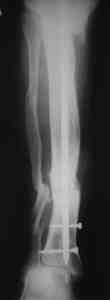

Пример (пациент 46 лет, лечился у нас 4 года назад, внутренний остеосинтез выполнен с определенными погрешностями, но перелом сросся и рецидива инфекции не было): рис. 1,2 - при переводе к нам в институт, рис. 3 - после микрохирругической пластики, рис. 4, 5 - после интрамедуллярного остеосинтеза, рис. 6, 7, 8 - внешний вид и рентгенограммы после окончания лечения

Штифт лучше взять неканюлированный, диаметр 10-11 мм. с большим количеством отверстий для блокирования (лучше ввести все блокирующие винты для создания максимальной стабильности).